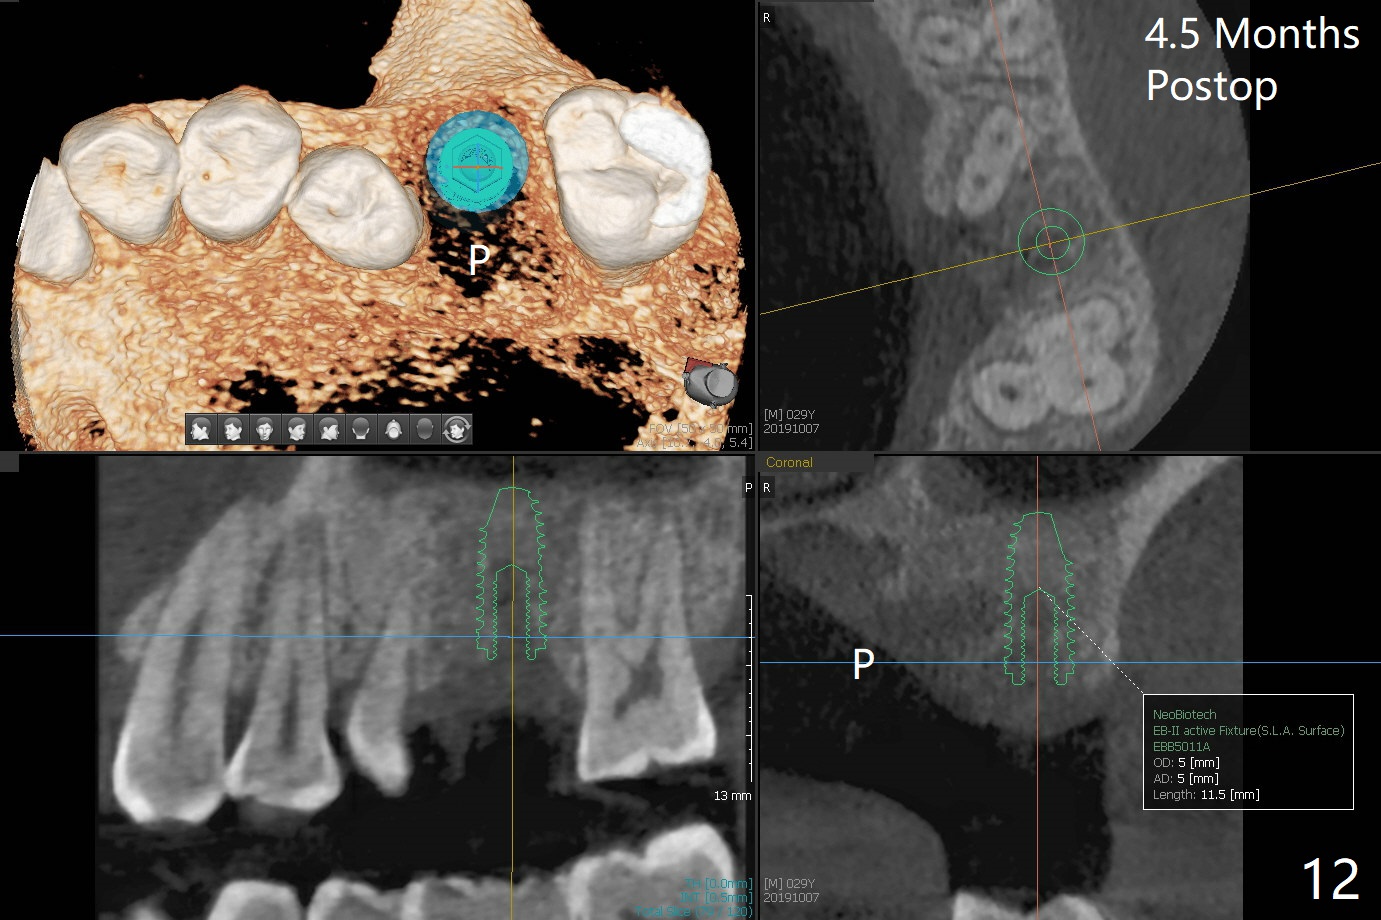

A 29-year-old man has pain in the upper left quadrant. It appears that the tooth #14 has endo and post failure with palatal fistula (Fig.1,2). The septum is almost non-existent; the palatal wall is low, while the sinus floor is present. Sticky bone is placed first against the defective palatal wall and presumably pushed as high as to the sinus floor (Fig.3-5). PRF plug/membrane and 6-month membrane are used to close the socket with 4-0 Chromic gut suture apparently securely, followed by periodontal dressing. Examination of the extracted tooth shows granulation tissue between the roots (Fig.6 *). Underneath the granulation tissue is cement-like material (Fig.7 C). Distal-to-mesial X-ray examination shows possible furcation perforation (Fig.8 *), while mesial-to-distal one the cement-like material in the furca and pulpal chamber as well as MB2 (Fig.9 >). The patient returns 8 days postop, reporting pain reduction, but wants to have #16 extracted. The periodontal dressing is loose, but stuck with 2 sutures underneath. When the dressing is removed, the wound looks normal (Fig.10). In fact the dressing is re-applied. The 6-month membrane has lost 1 month postop. The majority of the socket heals except the palatal (Fig.11 *), as related to the existing palatal fistula/defect (^). Orthodontics is being considered. If the buccal plate collapses 4.5 months post extraction, socket shield should have been done. In fact the buccal plate is robotic, while the bone density is low palatal in CT (Fig.12).